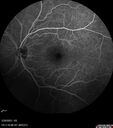

Advanced age-related macular degenerationvu 251 fois87 year old female. Severe macular bleed 15 years ago OD. Now with disciform scar. Left eye has progressing geographic atrophy.

VA OD: HM, OS: 5/200. IOP normal OU17 Mars 2024